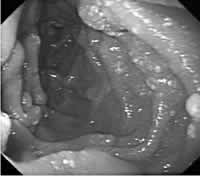

心脏超声发现极少量心包积液,腹部B超正常,口服小肠造影正常;胃镜显示:胃窦黏膜不平、水肿,呈弥漫小结节状,无充血;十二指肠球部、球后及降部黏膜轻度水肿,散在白点样改变(图1)。结肠镜:末段回肠黏膜呈绒毛状和白点样改变。十二指肠及末段回肠黏膜活检病理示小肠黏膜下淋巴管扩张。

原发性小肠淋巴管扩张症临床罕见,病程隐匿,表现多样,诊治过程中易被忽视。提高对本病的认识,尽早完善内镜、核素淋巴管显像和淋巴管造影十分重要。内镜直视下可见病变肠黏膜水肿、肥厚,绒毛苍白呈棒状及大小不等的黄白色结节。病理活检可见黏膜下淋巴管扩张。核素淋巴管显像和淋巴管造影可直接观察到肠系膜淋巴管狭窄、曲张,可伴其他部位淋巴管异常。以上特异性的影像学表现都将对诊断提供极大帮助。